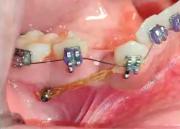

Dr. Franklin Novoa Flores – Especialista en Ortodoncia ortopedia – 72022459 Los microimplantes son pequeños tornillos de titanio, han ido evolucionando desde su aparición hasta la actualidad, con el fin de convertirse en un método apropiado para conseguir un anclaje... + más

APLICACIÓN DEL MICROIMPLANTE EN LA PRÁCTICA DE ORTODONCIA | El Diario